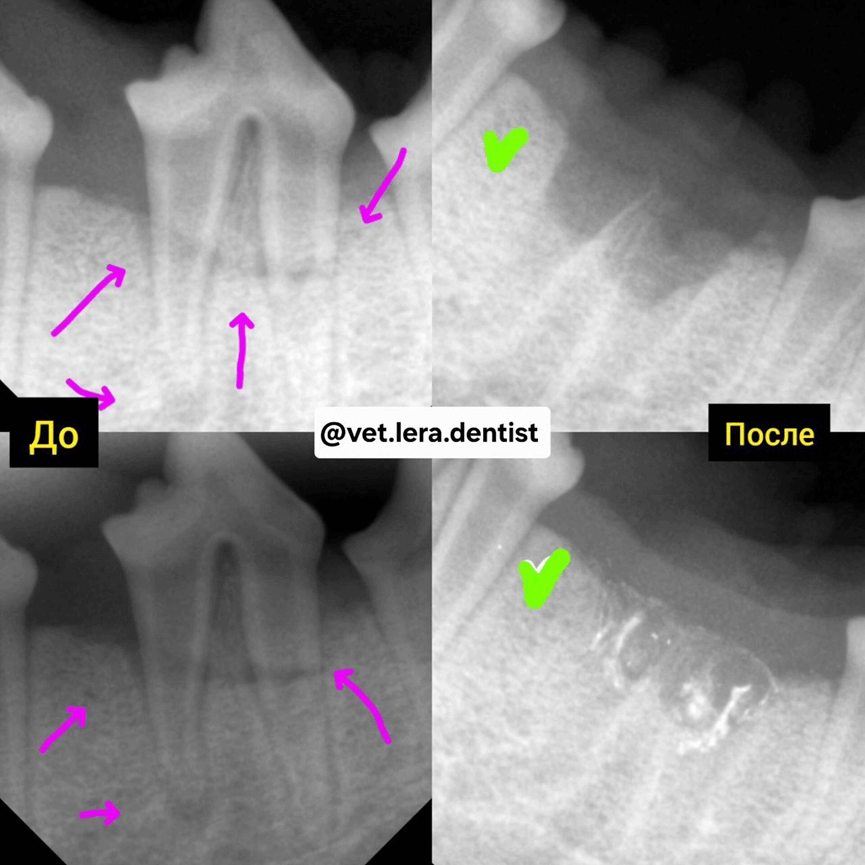

1-7-25092025.png

Фото 7.

Дентальный рентген. Лабрадор. 7 месяцев. До и после удаления сломанных корней зуба.

Фиолетовые стрелки — указывать на место перелома корней

В данном случае пациент не проявлял боли, более того он был активен, был хороший аппетит. Причина обращения — в том, что владелец заметил во время игры — кровь, подвижность зуба — поэтому на следующий день — обратился на приём.

1-9-25092025.png

Фото 8. Дентальный рентген верхних резцов. Брюссельский грифон. 2 года.

Стрелками указаны места переломов зубов.

И так же стрелками указано — полное удаление корней.

Данный пациент спрыгнул с дивана, в полете лаял — владелец видел удар мордой, заметил подвижность зубов — поэтому обратился на прием.